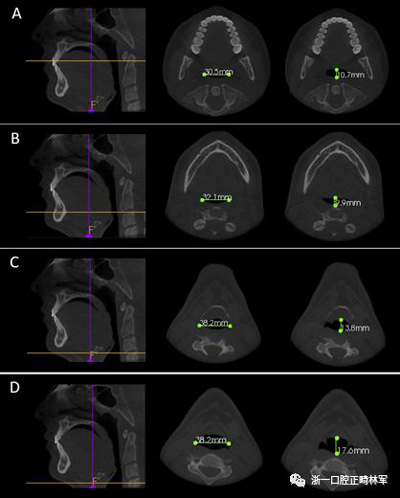

使用CS 3D成像軟件(版本3.4.3; Care-stream Health,Rochester,NY)進(jìn)行線性和角度測量。線性指標(biāo)包括鼻前后棘間距(ANS-PNS距離),咽腔最短距離(最短距離),咽腔C1的前后距離(APC1),咽腔C1的側(cè)壁間距離(LLC1),咽腔C2的前后距離(APC2),咽腔C2的側(cè)壁間距離(LLC2),咽腔C3的前后距離(APC3),咽腔C3的側(cè)壁間距離(LLC3),咽腔-會厭基底的前后距離(AP會厭),咽腔-會厭基底的側(cè)壁間距離(LL會厭),下頜骨兩側(cè)間的距離(L下頜骨),下頜骨的前后距離(AP下頜骨),舌骨兩側(cè)間的距離(L1舌骨)以及舌骨的前后距離(AP舌骨)。下頜骨前后角度的測量(下頜AP角),下頜橫角(TA下頜骨)和舌骨橫角(TA舌骨)。測量結(jié)果列于表I和圖1-4中。

圖2. A,LLC1和APC1; B,LLC2和APC2; C,LLC3和APC3; D,LL會厭和AP會厭。